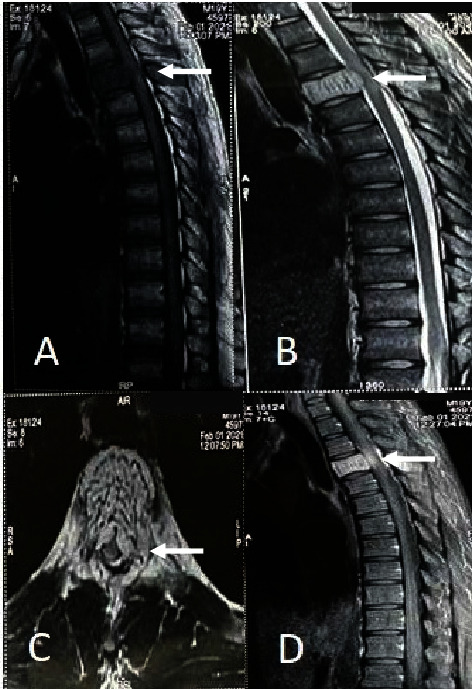

Aggressive thoracic hemangiomas are rare, benign tumors that extend into the spinal canal and cause neurological symptoms. Delayed diagnosis and treatment, due to a paucity of literature on optimal treatment strategies, can increase morbidity. This case report describes a 19-year-old male patient with aggressive thoracic hemangioma who presented with upper back pain and progressive weakness of the lower extremities. The patient underwent preoperative embolization and sclerotherapy, followed by decompression, posterior instrumentation, and stabilization. The final diagnosis was confirmed by biopsy, and there was a significant improvement in neurology after the surgical intervention. The diagnosis of rare lesions, such as aggressive hemangiomas, requires a high level of clinical suspicion and the assistance of imaging modalities in patients with features of compressive myelopathy. A combination of endovascular and surgical approaches can lead to optimal outcomes.